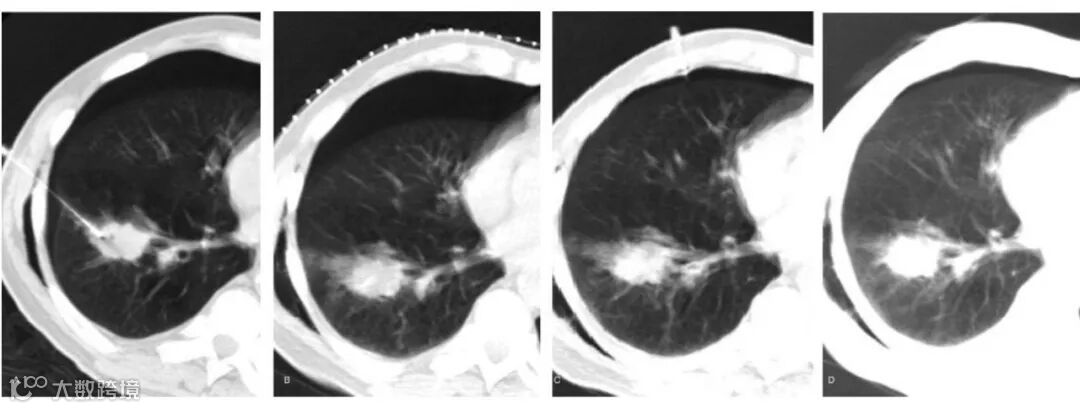

76岁女性,肺穿刺活检后气胸范围增大(A、B);更换穿刺点行气体抽吸(C);最后复查显示气胸明显好转(D)。